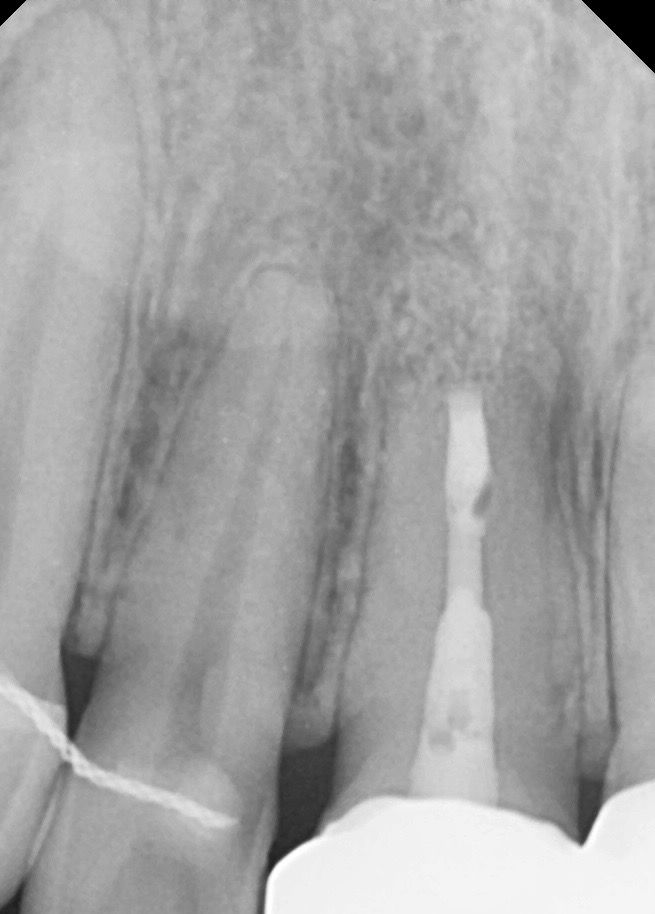

혹시몰라 치근단사진 올려둡니다 !

• 1번 째 사진

엑스레이 상으로는 염증이 보이진 않습니다. 일시적으로 치아가 예민해져서 그럴수 있습니다.

엑스레이 사진상 별 문제는 없어보입니다 일시적인 현상같습니다